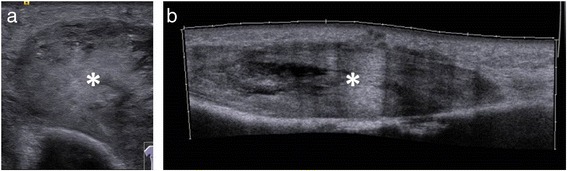

Figure 6.

Sonography of the upper arm shows the tumor (a & b; mark). A discrimination between abscess and soft-tissue tumor cannot be done.

The humerus x-ray was not adjuvant making differential diagnosis. Abscess, metastasis and soft tissue tumors could not be distinguished. Therefore a sonography was performed. A typical abscess formation, such as a cavity formation could not be demonstrated, thus a MRI was performed. The MRI was able to illustrate the size and dignity of the mass but a diagnosis still could not be confirmed.